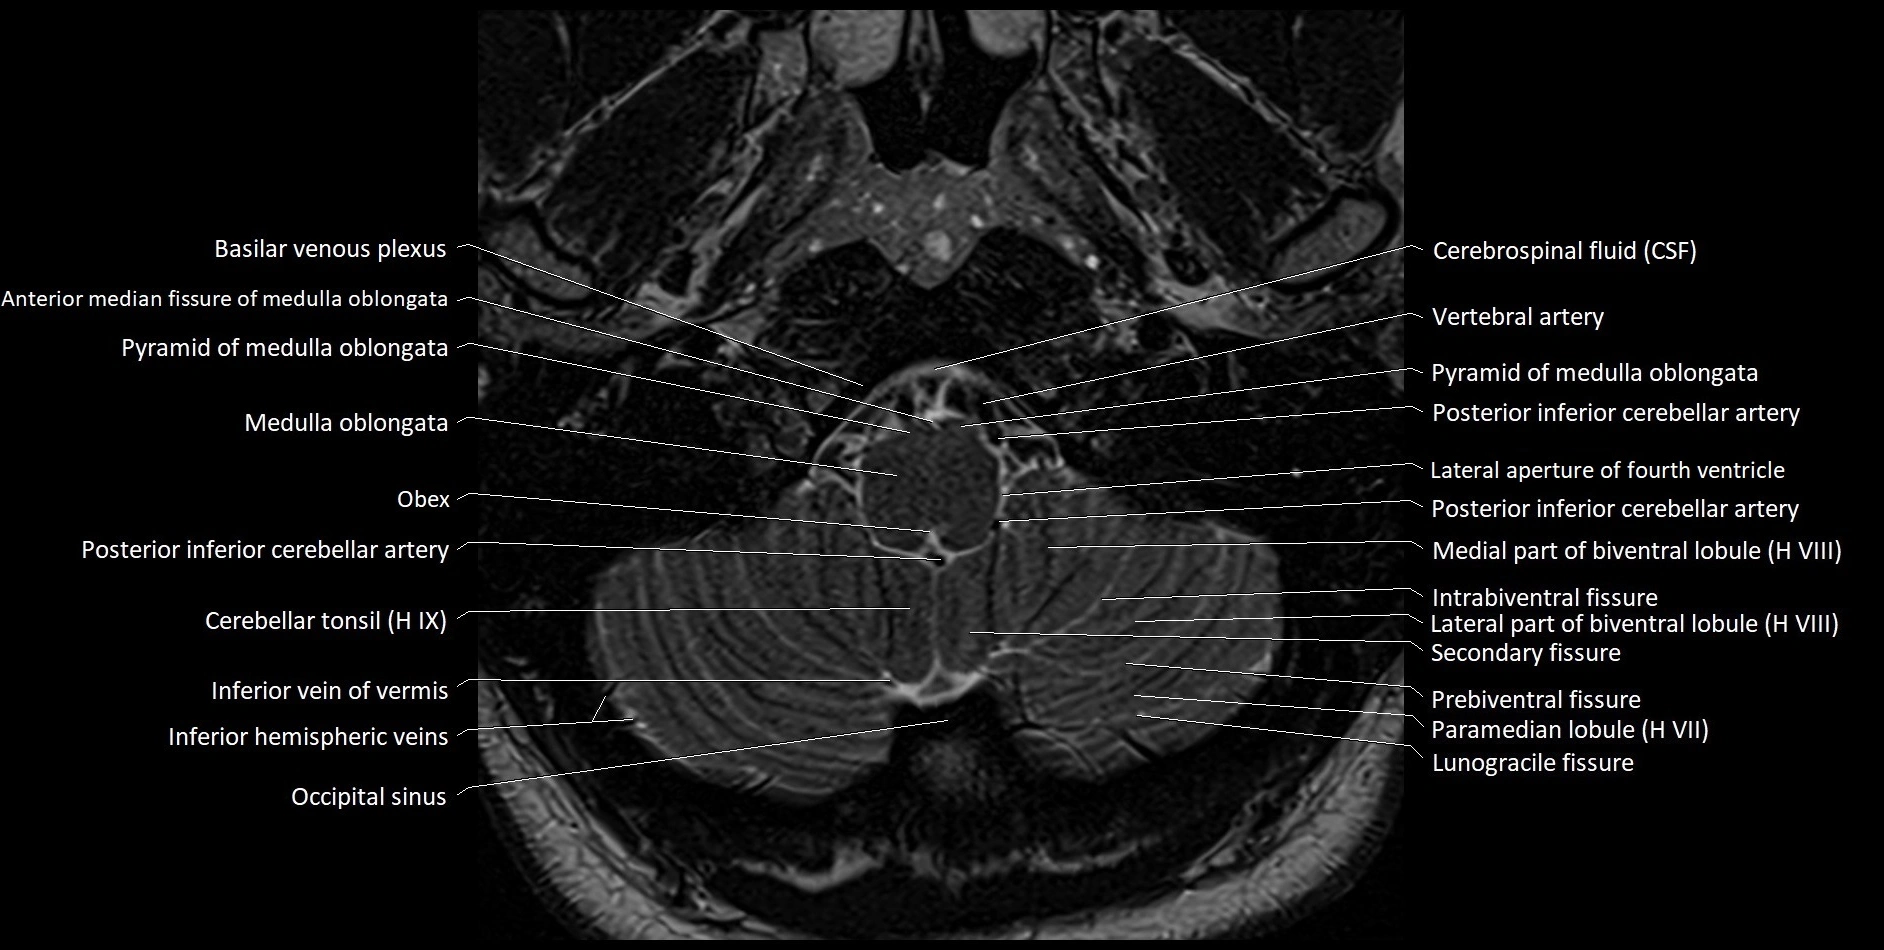

Experience the next generation of cross-sectional anatomy with our advanced 3T MRI, enhanced by AI-powered Deep Resolve reconstruction. Our ultra-high-resolution imaging (0.3–0.7 mm in-plane resolution) combined with ultra-small field-of-view techniques reveals fine anatomical detail with exceptional clarity, redefining anatomical visualization and education.

Explore an advanced library of ultra-high-resolution MRI anatomy, developed from hundreds of repeated scans of volunteers using cutting-edge 3T scanners, dedicated coils, and AI-powered enhancement. These images capture real anatomical detail, revealing even the smallest microstructures while preserving the authenticity of true clinical imaging without over-reliance on virtual labeling.

Learn MRI anatomy like never before—49 body parts, 144 planes

Crystal-clear, high-res images for effective large-screen teaching

All our cross-sectional images are meticulously hand-labeled by professionals with over 20 years of experience in cross-sectional imaging. This is the result of over six years of dedicated work, precision, and passion. Every image is individually checked and verified by senior consultant radiologists from major London NHS trusts, each with relevant subspecialty expertise—ensuring the highest level of accuracy and clinical relevance.